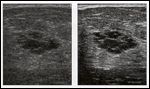

At left, a conventional ultrasound image of a breast cyst considered indeterminate. At right, the same cyst as seen in a coded harmonic ultrasound image obtained from the identical position. Images were obtained with a stationary 7-MHz linear transducer. Ultrasound images courtesy of Dr. Supriya Kulkarni, University Health Network, Mt. Sinai Hospital, Toronoto Canada.

The study included 117 image pairs from 30 consecutive patients with indeterminate cysts on conventional imaging. Each pair consisted of a conventional image and a harmonic image obtained from identical positions with a stationary 7-MHz linear transducer (see Figure). Indeterminate cysts were defined as cysts with internal echoes, ill-defined walls, or poor posterior enhancement.